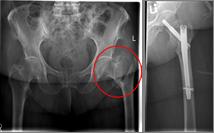

In addition to a thorough physical examination, radiographs of the pelvis and the affected hip are crucial for the diagnosis.

Oberschenkel 1          Oberschenkel 2

Images: Here is the supply of a dynamic hip screw shown.

In younger patients and a minor shift, the goal is to preserve the femoral head. The blood supply to the femoral head is at risk for medial femoral neck fractures, so that the fastest possible care should be sought if one wants to preserve the femoral head. Among others, the dynamic hip screw (DHS) is available for this purpose.